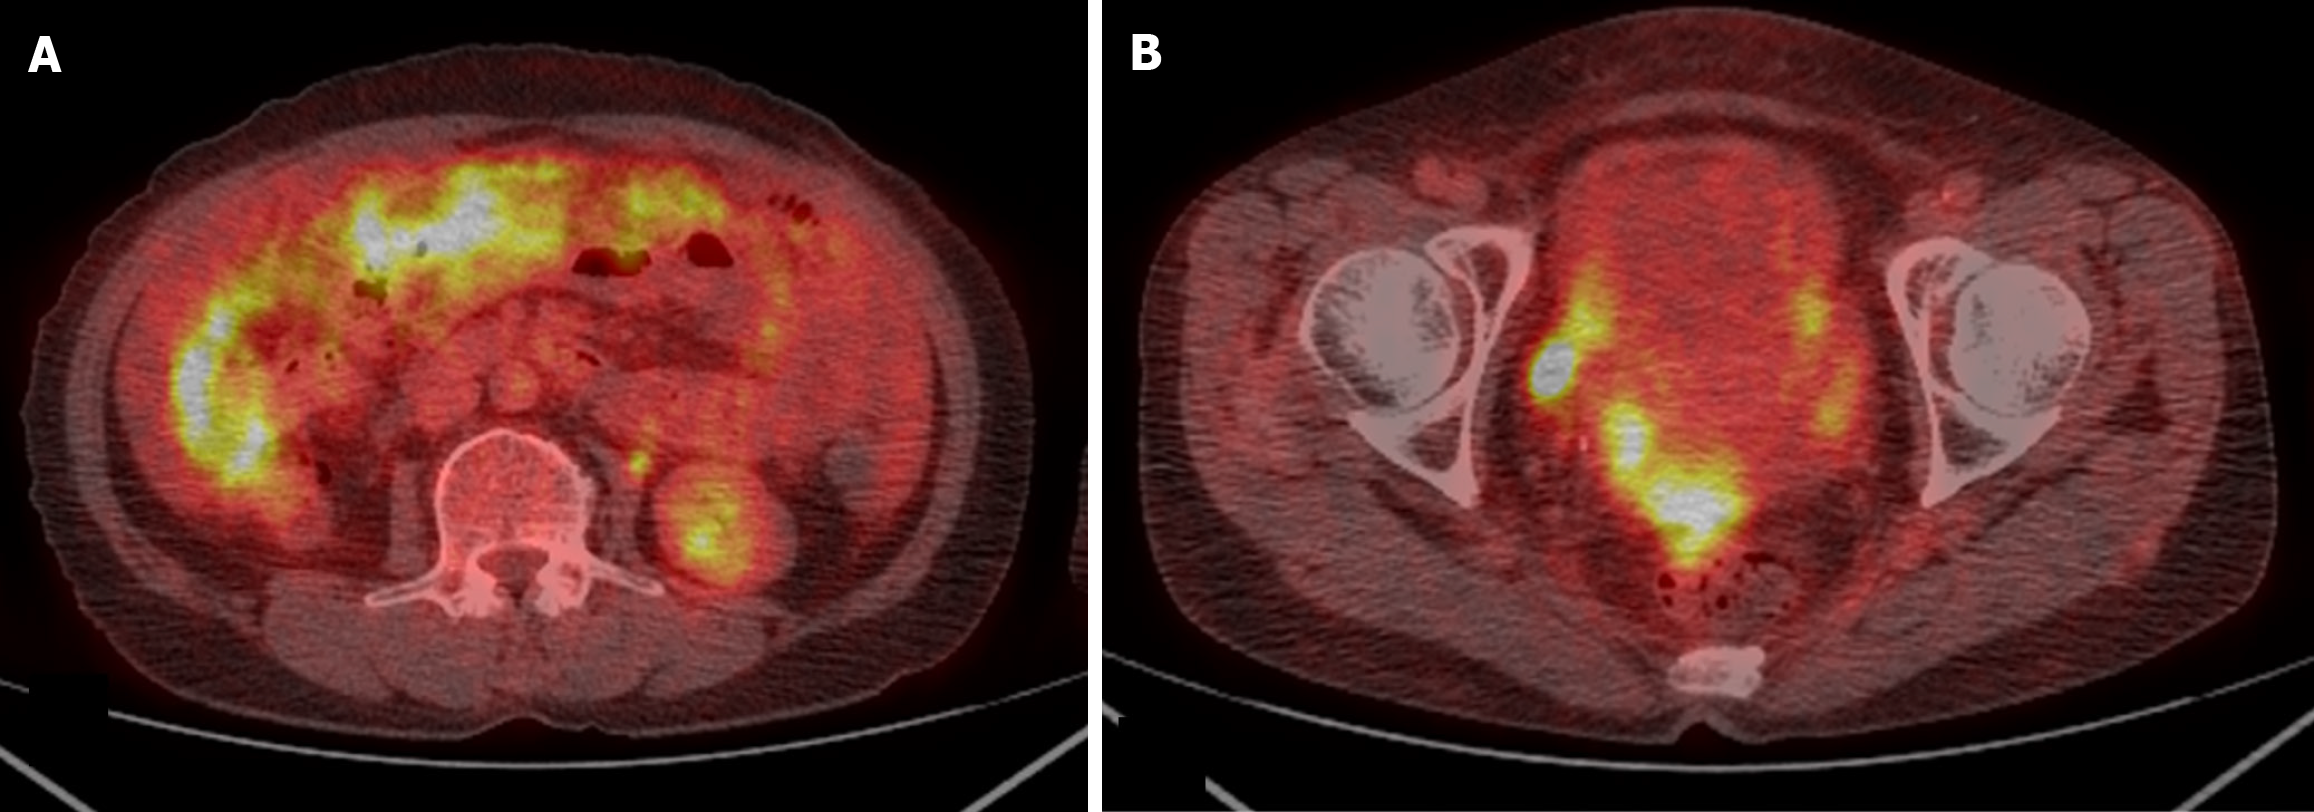

Abdominal-pelvic (AP) computed tomography (CT) revealed moderate to large volumes of diffuse ascites; smudged, nodular omentum in the abdomen and pelvic cavity; and focal abutting or invasion of the anterior wall of the mid-rectum in the cul-de-sac area (Figure 1). An ulcerofungating mass (4 cm in diameter) was observed 45 cm from the anal verge during colonoscopy (Figure 2A), and the histological results confirmed moderately differentiated adenocarcinoma. Positron emission tomography (PET)-CT revealed a substantially elevated metabolic uptake in the abdomen, suggestive of peritoneal seeding (Figure 3).

For patients with CRC and PM, CT is the predominant imaging modality for the evaluation of tumor size and extent, with a reported sensitivity of 75%, specificity of 92%, positive predictive value of 90%, and negative predictive value of 79% for 64-row CT[25]. The reported average sensitivity is 89% for lesions ≥ 0.5 cm, whereas it was merely 43% for those measuring < 0.5 cm[26]. Additionally, CT-based assessment of factors determining complete resection of the neoplasm remains challenging, as the detection rate for tiny, localized lesions, such as diffuse peritoneal, small-intestinal, and mesenteric involvement, is low. To compensate for the low detection rate of CT in these regions, magnetic resonance imaging and PET-CT examinations are conducted, but they remain sufficient. In this case, although the smudged, nodular omentum upon CT and the significantly elevated metabolic uptake in the relevant area upon PET-CT were suggestive of peritoneal carcinomatosis, the diffuse peritoneal, small-intestinal, and mesenteric involvement could not be anticipated preoperatively.